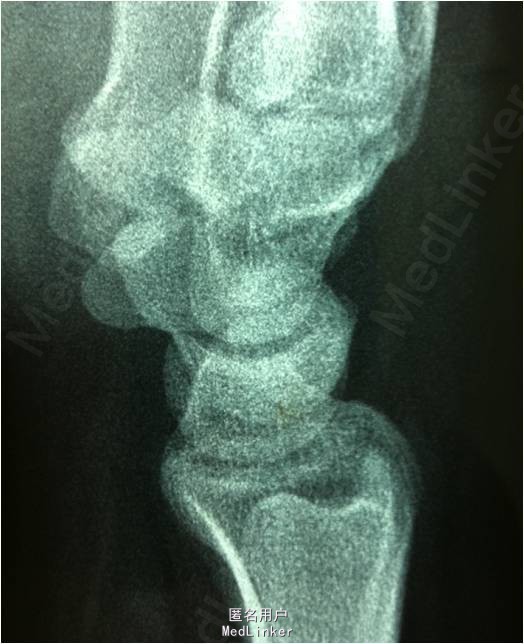

患者男,30岁,因”摔伤致右腕关节疼痛2周余”入院。患者2周前因摔伤后出现右腕关节疼痛,伴活动障碍。现患者为求进一步诊治前来我院就诊,余未见明显异常。

查体:右腕关节稍肿胀,腕关节桡侧间隙压痛,石膏固定良好,无皮损,无骨摩擦音。肢端血运、感觉、运动可,肌力5级。 X线检查提示:右腕舟状骨骨折

诊断:右腕舟状骨骨折。拟行右腕关节镜检,关节镜监视下行腕舟骨骨折复位内固定(备开放)术。